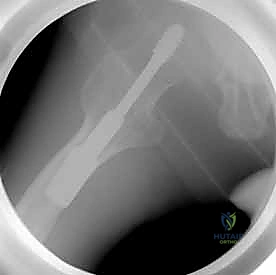

لماذا نستخدم 3 مسامير؟ (هندسة المثلث المقلوب)

يعتمد الأستاذ الدكتور محمد هطيف على مبادئ الميكانيكا الحيوية (Biomechanics) في التثبيت. يتم عادةً إدخال ثلاثة مسامير متوازية في عنق الفخذ. لا يتم وضعها بشكل عشوائي، بل تُرتب في شكل مثلث مقلوب (Inverted Triangle):

1. المسمار السفلي (Inferior Screw): يُوضع أولاً ليكون الدعامة الأساسية التي تستند على الكورتيكس السفلي الصلب لعنق الفخذ (Calcar)، وهو يتحمل أكبر قدر من وزن الجسم.

2. المسمار الأمامي العلوي (Antero-superior Screw).

3. المسمار الخلفي العلوي (Postero-superior Screw).

هذا التوزيع الثلاثي يوفر ثباتًا دورانيًا (Rotational Stability) ممتازًا ويمنع رأس الفخذ من الانزلاق أو الدوران حول محوره، كما يسمح بانضغاط الكسر (Compression) على طول خط الكسر، مما يحفز الخلايا العظمية على الالتئام السريع.